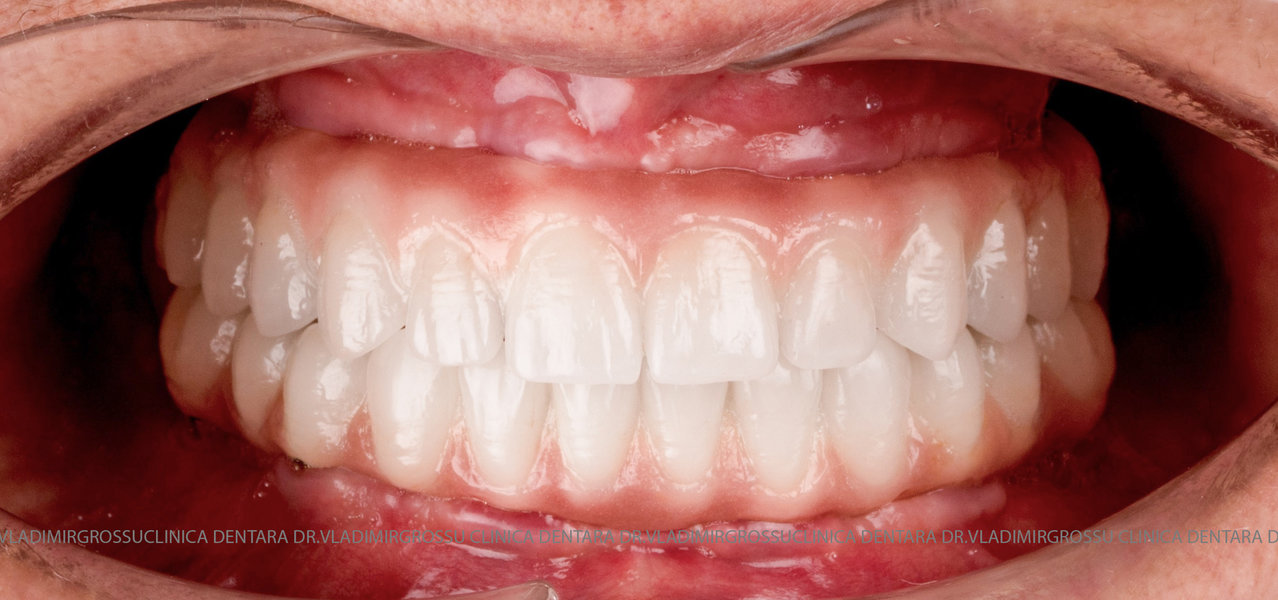

Cazuri clinice conceptul All-on-6